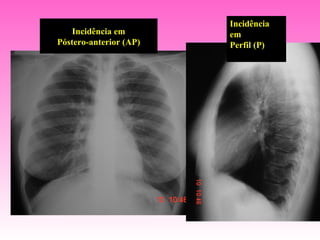

Incidência

Incidência em       em

Póstero-anterior (AP)   Perfil (P)